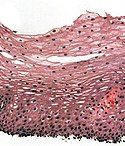

Normal esophagus

General:

- Stratified squamous non-keratinized epithelium.

Normal (esophageal) squamous epithelium:

- Should "mature" to the surface like good stratified squamous epithelium does.

- No nuclei at luminal surface.

- Cells should become less hyperchromatic as you go toward the lumen.

- Mitoses should be rare and should NOT be above the basal layer.

- Inflammatory cells should be very rare.